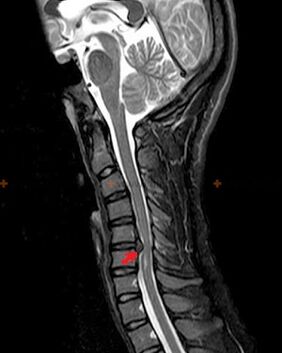

Diagnostice și semne cu raze X

Pentru diagnosticarea osteocondrozei se folosesc următoarele metode de cercetare: radiografie (de preferință cu teste funcționale), MSCT și RMN. Ultimul studiu este cel mai de preferat datorită faptului că permite vizualizarea foarte clară a stării structurilor intervertebrale.

Prezența modificărilor descrise mai sus, precum și modificările structurii discului intervertebral, detectate prin MSCT și RMN, servesc drept semne de încredere care confirmă prezența osteocondrozei.